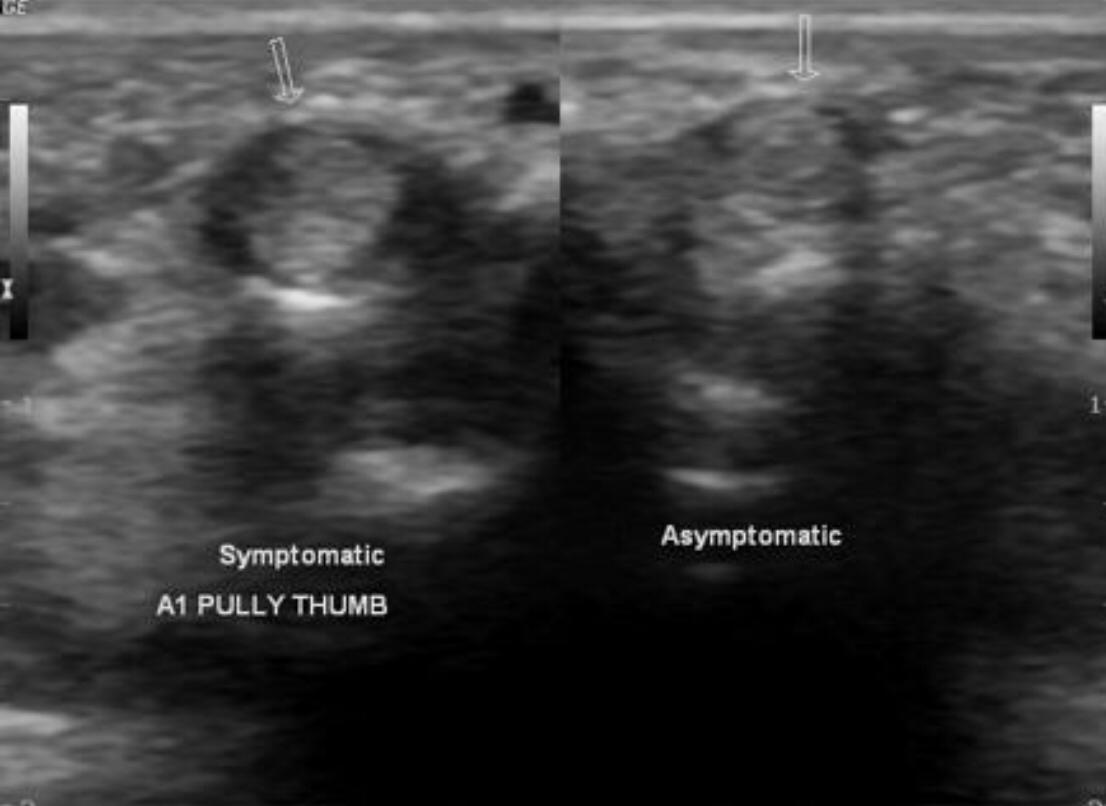

Trigger finger is a type of stenosing tenosynovitis. It develops due to repetitive microinjury from frequent flexion-extension movements of the fingers.

Thickening and hyper-vascularization of the A1 pulley are the hallmarks of trigger fingers on sonography. Other frequently observed features include distal flexor tendinosis and tenosynovitis.

The first annular pulley (A1) at the metacarpal head is by far the most often affected pulley in trigger finger, though cases of triggering have been reported at the second and third annular pulleys (A2 and A3, respectively), as well as the palmar aponeurosis.

The level of thickening can be variable with some authors suggesting the normal value being around 0.5 mm with thickening suggested when the diameter is over 1.1 mm.

The condition can be conservatively managed with splinting, NSAIDs, and local steroid injections or may require a surgical section of the A1 pulley when the pulley is markedly thickened.